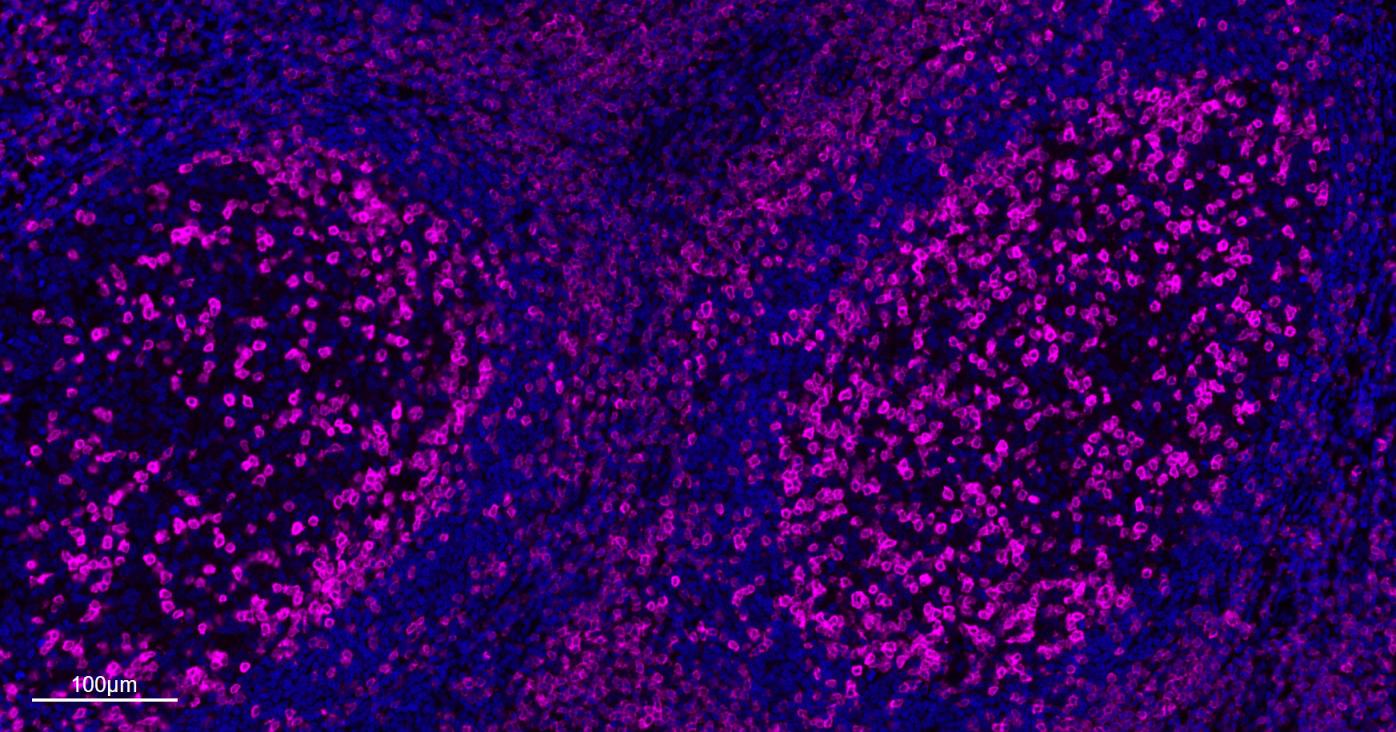

IFHuman, Mouse, Rat1:500-2000